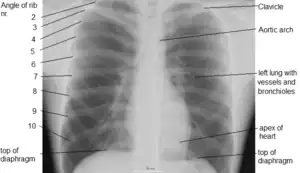

Different views (also known as projections) of the chest can be obtained by changing the relative orientation of the body and the direction of the x-ray beam. The most common views are posteroanterior, anteroposterior, and lateral. In a posteroanterior (PA) view, the x-ray source is positioned so that the x-ray beam enters through the posterior (back) aspect of the chest and exits out of the anterior (front) aspect, where the beam is detected. To obtain this view, the patient stands facing a flat surface behind which is an x-ray detector. A radiation source is positioned behind the patient at a standard distance (most often 6 feet, 1,8m), and the x-ray beam is fired toward the patient.

Landmarks

In the average person, the diaphragm should be intersected by the 5th to 7th anterior ribs at the mid-clavicular line, and 9 to 10 posterior ribs should be viewable on a normal PA inspiratory film. An increase in the number of viewable ribs implies hyperinflation, as can occur, for example, with obstructive lung disease or foreign body aspiration. A decrease implies hypoventilation, as can occur with restrictive lung disease, pleural effusions or atelectasis. Underexpansion can also cause interstitial markings due to parenchymal crowding, which can mimic the appearance of interstitial lung disease. Enlargement of the right descending pulmonary artery can indirectly reflect changes of pulmonary hypertension, with a size greater than 16 mm abnormal in men and 15 mm in women.[6]

Appropriate penetration of the film can be assessed by faint visualization of the thoracic spines and lung markings behind the heart. The right diaphragm is usually higher than the left, with the liver being situated beneath it in the abdomen. The minor fissure can sometimes be seen on the right as a thin horizontal line at the level of the fifth or sixth rib. Splaying of the carina can also suggest a tumor or process in the middle mediastinum or enlargement of the left atrium, with a normal angle of approximately 60 degrees. The right paratracheal stripe is also important to assess, as it can reflect a process in the posterior mediastinum, in particular the spine or paraspinal soft tissues; normally it should measure 3 mm or less. The left paratracheal stripe is more variable and only seen in 25% of normal patients on posteroanterior views.[7]